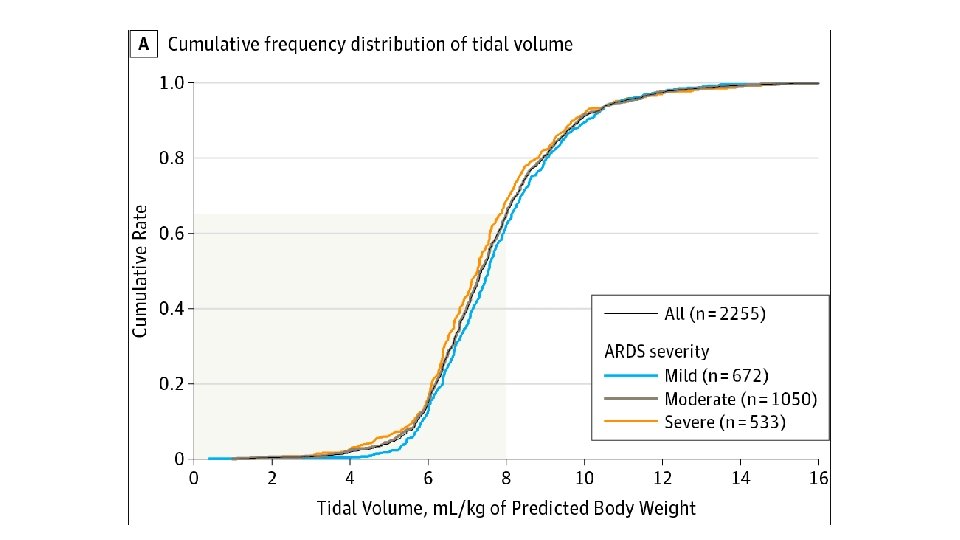

• Tidal Volume (VT) • ARDSnet Trial (Landmark Study) • Tidal volume should be indexed to lean body weight (LBW) • Tidal volumes >10 ml/kg shown to increase VALI and mortality • Low tidal volume ventilation gradually became accepted standard of practice (6 m. L/kg)

Lung Protective Ventilation • Ideal mechanical ventilation to avoid VALI • Volume of aerated lung in ARDS is reduced, hence VT and pressures considered safe for uninjured lung can cause regional overdistension further injuring the epithelium and amplifying inflammation (volutrauma and barotrauma) • Repetitive opening and closing of lung units (atelectrauma) amplifies regional lung strain and denatures surfactant • Epithelial and endothelial injury results in translocation of proinflammatory mediators and bacterial products, leading to worsening systemic inflammation (biotrauma)

Lung Protective Ventilation • • • VT not greater than 6 m. L/kg Pplateau <30 cm. H 2 O (Ppeak <35 cm. H 2 O) PEEP Permissive hypercapnia Fi. O 2 to maintain Sp. O 2>92% Typically a resitrictive fluid strategy